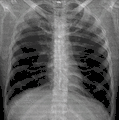

تصوير الصدر بالأشعة السينية

تصوير الصدر بالأشعة السينية أو ما يعرف باسم (CXR) اختصارا لـ (chest x-ray) هو تصوير إسقاطي للصدر يستخدم في تشخيص الأمراض الرئوية ، أمراض القلب والأوعية، الأمراض التي تصيب عظام القفص الصدري أو العمود الفقري، السرطانات المتولدة في المنطقة أو المهاجرة إليها بـالانبثاث من أعضاء أخرى في الجسم.[1][2][3]

صورة أشعة صدرية ذات جودة عالية.

صورة إشعاع صدرية لالتهاب رئوي في الجهتين اليمنى واليسرى.